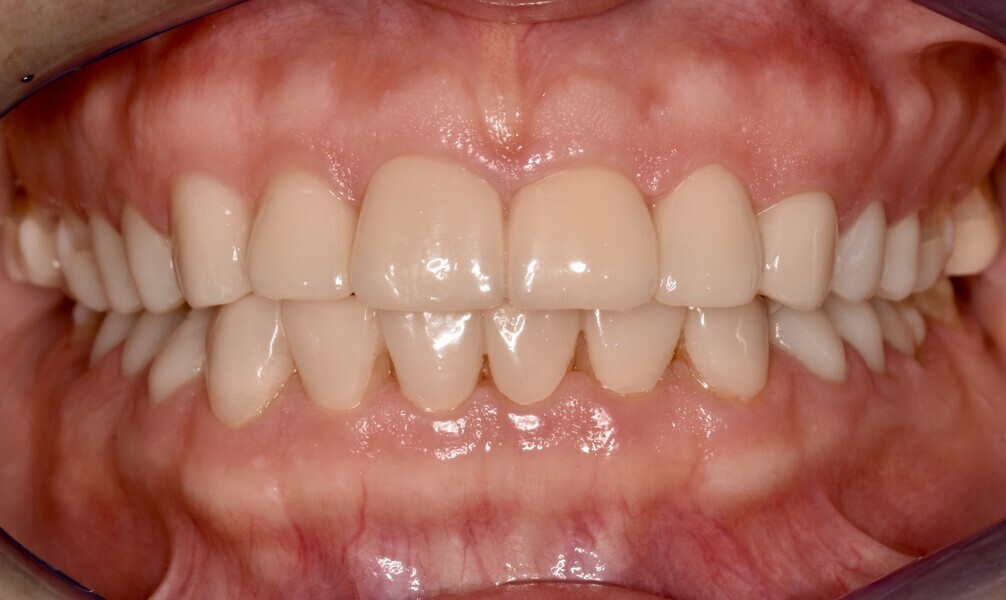

Fig. 1a: Initial situation. Recognisable loss of vertical dimension in the frontal view.